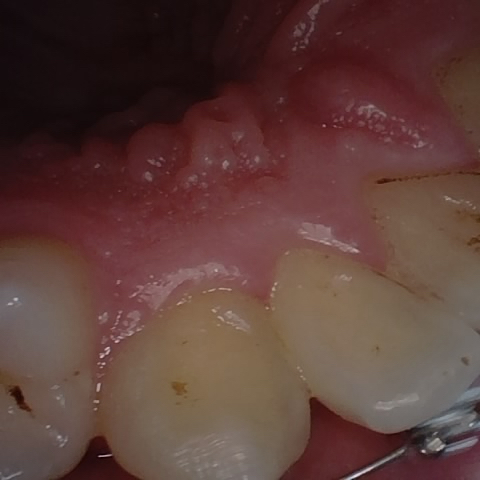

Image 1499 / 2000

NHD39969

Annotated as "Good"

Original Image Rendering Image